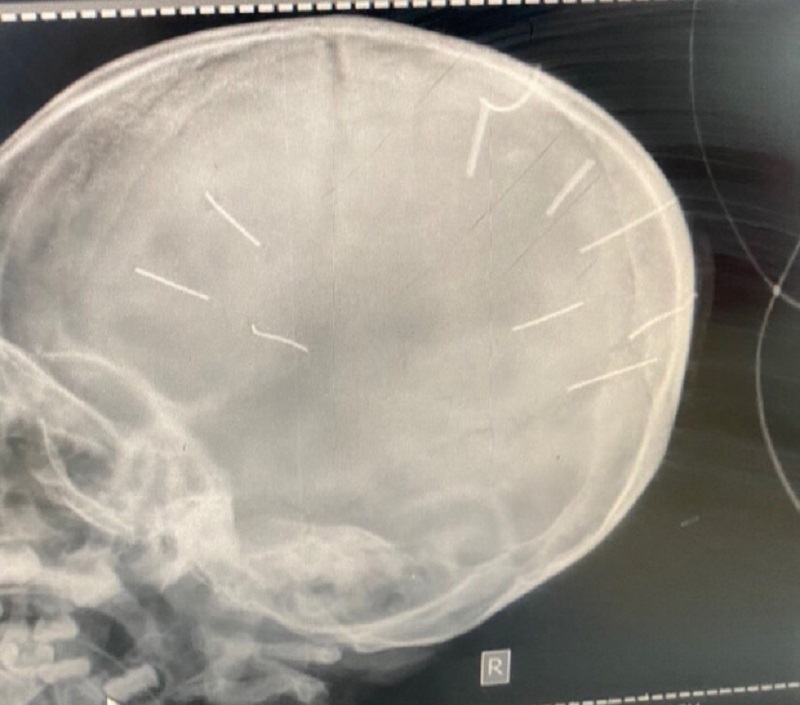

Đối tượng nghi ghim đinh vào đầu bé gái 3 tuổi bị câm điếc bẩm sinh

25/01/2022 17:22:35

Đối tượng chính ghim đinh vào cháu bé 3 tuổi là người tình của mẹ cháu bé. Người này bị câm điếc bẩm sinh.